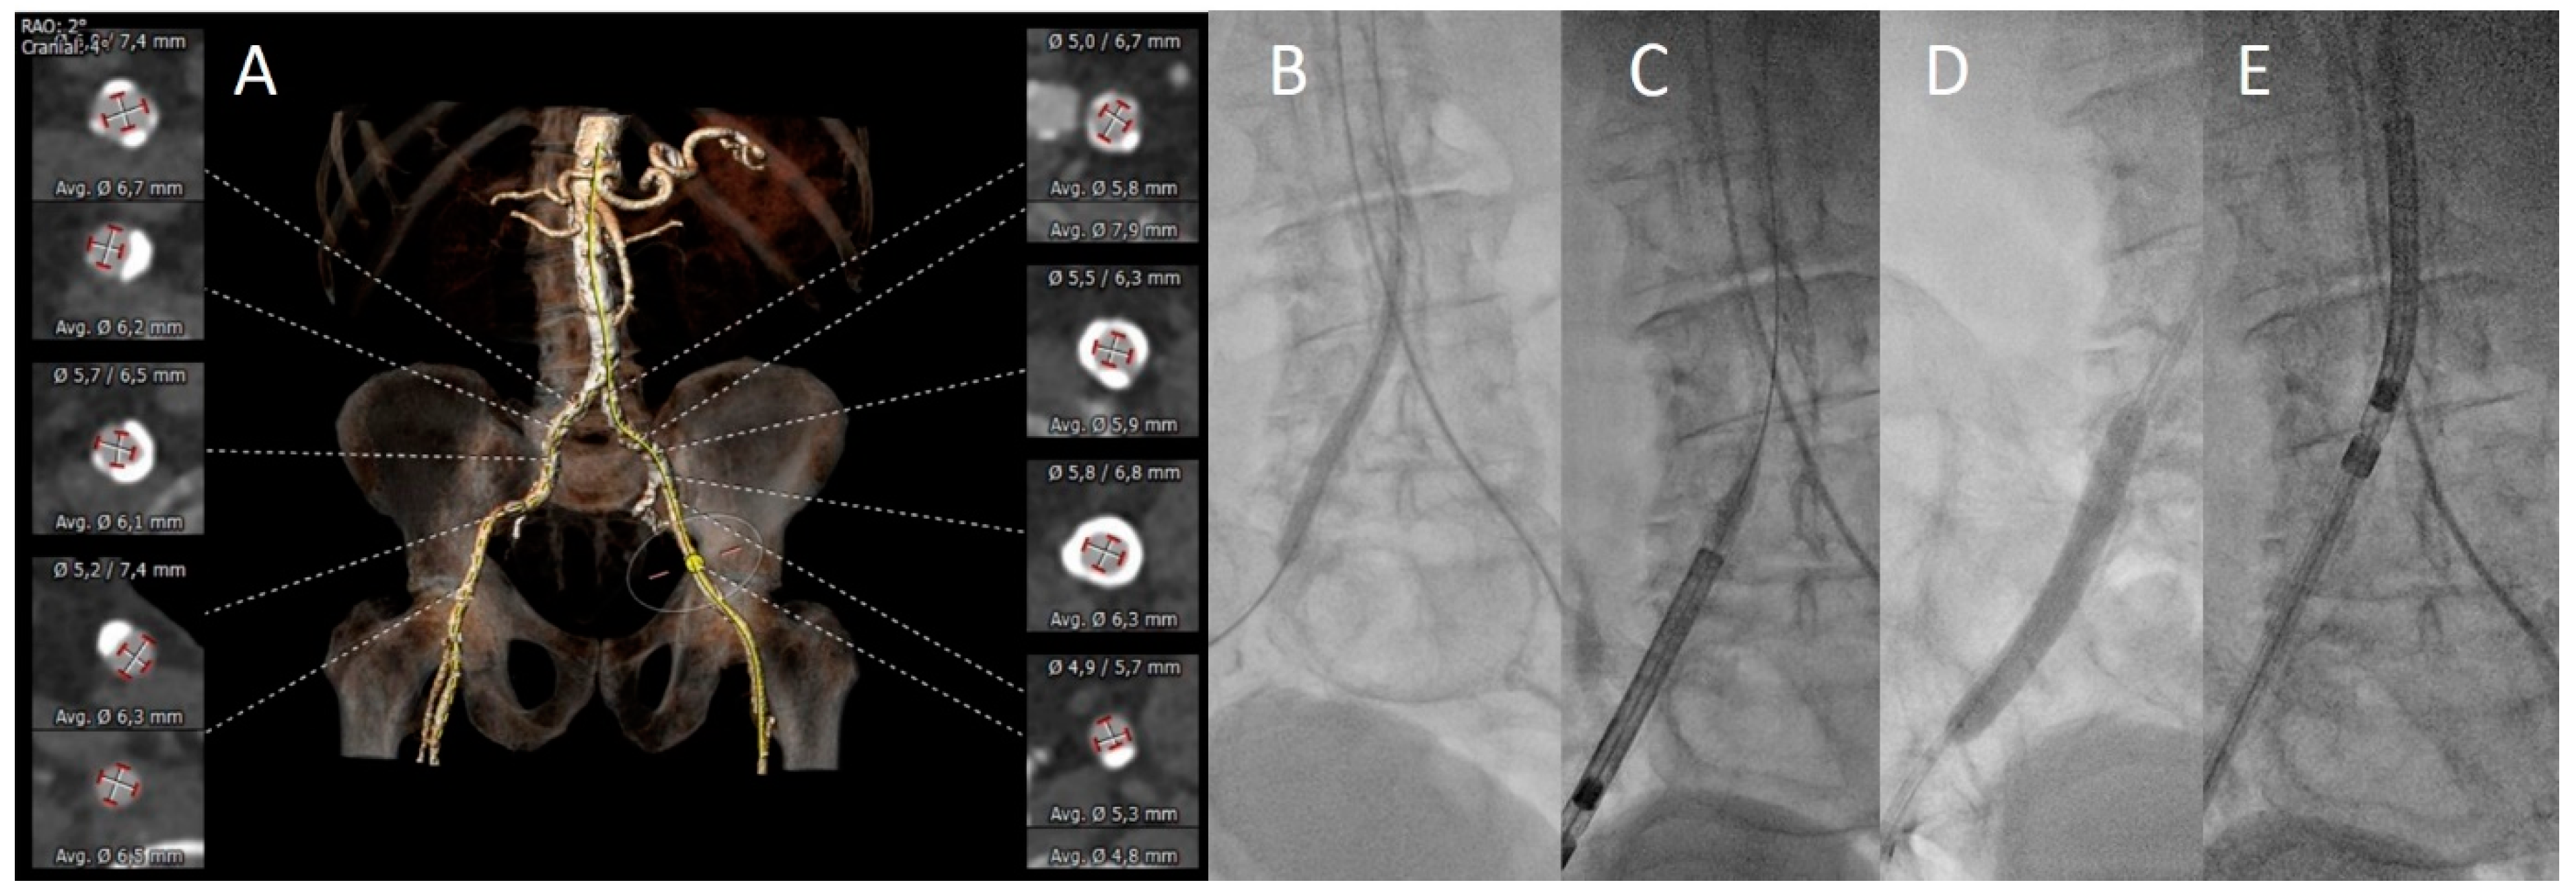

3.2. Vascular Assessment

3.3. Procedural Aspects